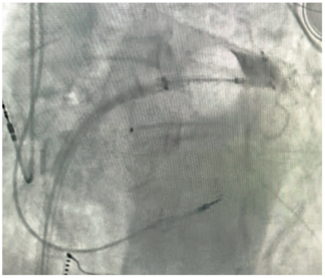

Armin Kiankhooy, MD, and colleagues share an evolved iteration of the Convergent procedure, also known as Convergent “Plus.”